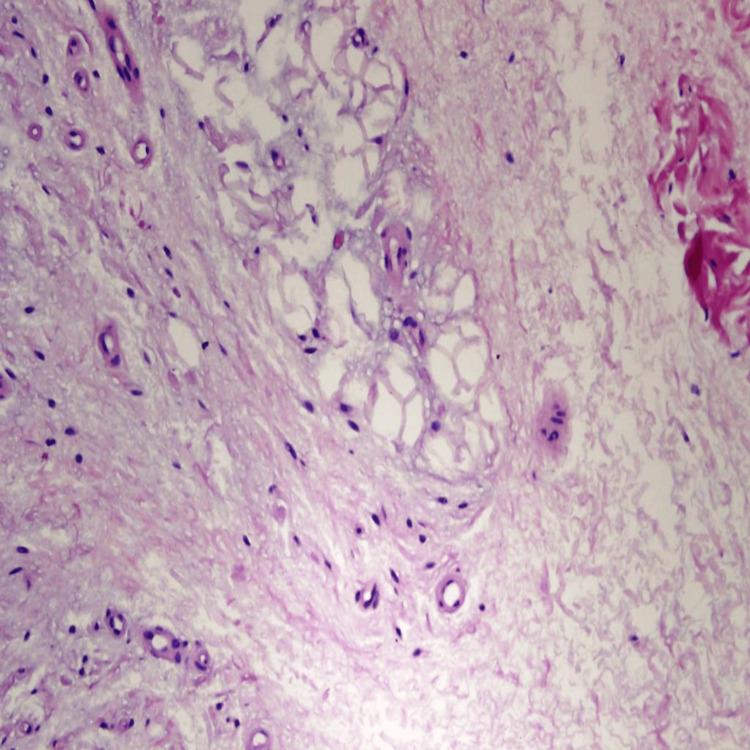

Sneddon syndrome, also known as livedo reticularis with cerebrovascular accidents, is a rare but chronic condition that affects blood vessels in the skin and brain. This syndrome is characterized by a net-like appearance on the skin, known as livedo reticularis, which occurs due to the constriction of blood vessels. In addition to skin manifestations, Sneddon syndrome is often associated with repeated neurological events, such as strokes or transient ischemic attacks. These neurological symptoms can vary in severity and can lead to various complications. Upon admission to the stroke unit, a 28-year-old female was found to have bilateral livedo reticularis affecting the soles and the dorsal sides of the hands. Patient evaluation is done through medical history, physical examination, routine laboratory tests, and other diagnostic procedures.

斯内登综合征,也称为伴有脑血管意外的网状青斑,是一种罕见的慢性疾病,会影响皮肤和大脑中的血管。这种综合征的特征是皮肤上出现网状外观,即网状青斑,这是由血管收缩引起的。除了皮肤表现外,斯内登综合征还常与反复的神经系统事件相关,如中风或短暂性脑缺血发作。这些神经症状的严重程度各不相同,并可能导致各种并发症。一名28岁女性入住卒中单元时,被发现双侧网状青斑累及足底和手背。通过病史、体格检查、常规实验室检查和其他诊断程序对患者进行评估。